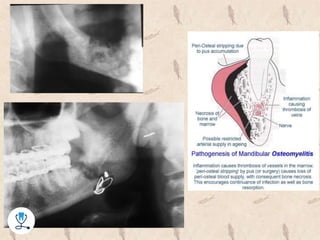

‫استئومیلیت‬

•‫تعریف‬

–‫لغوی‬:‫استخوان‬ ‫مغز‬ ‫التهاب‬

–‫کلینیکی‬:‫استخوان‬ ‫در‬ ‫عفونت‬

–‫مغ‬ ‫بسته‬ ‫فضای‬ ‫در‬ ‫نرم‬ ‫بافت‬ ‫ادم‬ ‫و‬ ‫التهاب‬ ‫موجب‬ ‫اسفنجی‬ ‫استخوان‬ ‫به‬ ‫ها‬ ‫باکتری‬ ‫تهاج‬‫ز‬

‫استخوان‬

•‫مندیبل‬ ‫از‬ ‫تر‬ ‫زیاد‬ ‫رسانی‬ ‫خون‬ ‫دلیل‬ ‫به‬ ‫کمتر‬ ‫شیوع‬ ‫ماگزیال‬ ‫در‬

•‫پائین‬ ‫فک‬ ‫در‬ ‫کننده‬ ‫مستعد‬ ‫عوامل‬ ‫مهترین‬:

–‫قبلی‬ ‫دندانی‬ ‫های‬ ‫عفونت‬–‫مندیبل‬ ‫های‬ ‫شکستگی‬

–‫،سوتغ‬ ‫دیابت‬ ، ‫الکلیسم‬ ‫مانند‬ ‫یابد‬ ‫می‬ ‫افزایش‬ ‫میزبان‬ ‫دفاع‬ ‫ضعف‬ ‫با‬ ‫ولی‬ ‫کم‬ ‫خیلی‬‫شیمی‬ ، ‫ذیه‬

‫و‬ ‫درمانی‬.....

•‫رادیوگرافی‬ ‫نمای‬

–‫یافته‬ ‫افزایش‬ ‫رادیولوسنسی‬

–‫خورده‬ ‫بید‬ ‫نمای‬